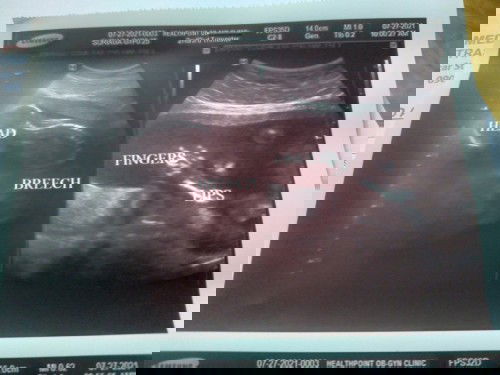

Breech position

Hi mga Momsh! Ask lng ano po gagawin if breech position c baby. 20weeks plng po ako. Pwde pa po ba mg normal delivery ako.. #1sttimeMomHere